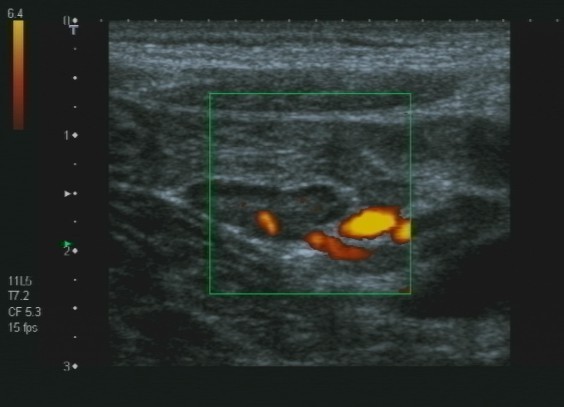

Lo studio medico privato del Dottor Patrizio Stornelli è ad Avezzano è dotato di un'attrezzatura ecografica moderna. Oltre alla ecografia addominale dei parenchimi, si esegue l'ecografia gastroenterolgica ed in particolare l'ecografia del tenue, che consente la diagnosi ed il follow-up particolaremente dei paziente con malattia di Crohn, ma anche l'ecografia del colon. Grazie a questo approccio è possibile scansionare interi segmenti del colon con particolare riguardo alla patologia diverticolare ma anche di indiduare l'appendice e di porre diagnosi di certezza di eventuale appendicite acuta.